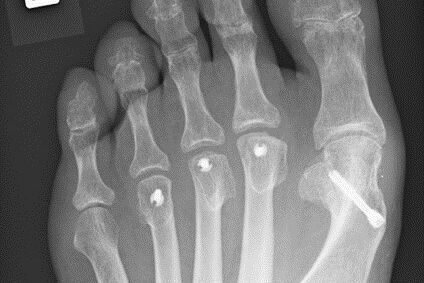

Therapie: distale Umstellung am MT1, Osteotomie an MT 2-4

Die operative Korrektur, bei der Umstellungsosteotomien an den Mittelfußknochen 1-4 links durchgeführt wurden, erfolgte im Mai 2018.

Bei anhaltenden Beschwerden wurde im Mai 2019 eine Röntgenaufnahme durchgeführt, die einen Schraubenüberstand von 1mm am Köpfchen des MT3 ergab. Dieser Befund wurde durch eine CT Untersuchung, bei der zusätzlich eine Arthrose im Grundgelenk der Großzehe und der zweiten Zehe gefunden wurde,  bestätigt.

Röntgenuntersuchungen

Der Schraubenüberstand sei auf der postoperativen Aufnahme, die nicht streng seitlich gewesen sei, nicht erkennbar gewesen.